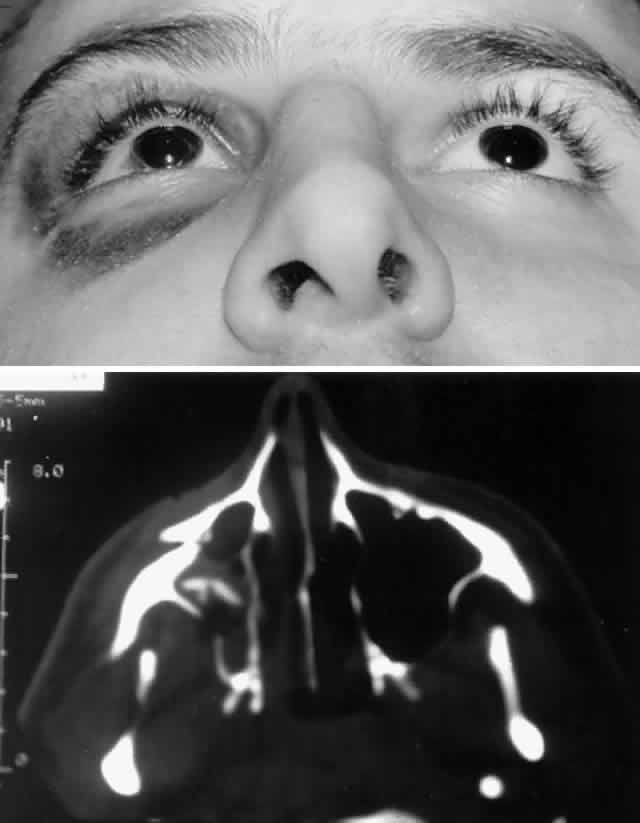

The position of the globe is also assessed (Fig. 3). As detailed previously, outward expansion of the orbital walls (blow-out fractures) can produce enophthalmos. Inward expansion of the orbital walls (blow-in fractures) can reduce orbital volume, potentially producing exophthalmos. In the early period after blunt orbital trauma, orbital edema and hemorrhage can transiently increase the orbital soft tissue volume, producing exophthalmos or “masking” the underlying potential for enophthalmos. As orbital edema subsides, the true globe position becomes evident. Over a more extended period of time (several months), soft tissue changes (cicatrization and, less commonly, fat atrophy) may contribute to the production of late enophthalmos. Globe position can be grossly assessed by direct visual inspection. Viewing the axial projection of the globes from above (“bird's-eye view”) or from below (“worm's-eye view”) facilitates a gross determination of axial globe position.

After the history and physical examination, consideration is given to further assessment of the orbital injury with radiologic imaging. The indications for radiologic imaging area are based on the physician's assessment of the injury and include gross orbital and facial deformity, limitation of ocular motility, and associated neurologic injuries. CT is the imaging modality of choice in the assessment of orbital/craniofacial fractures because it provides excellent detail of the bony injury as well as the orbital soft tissues in most cases (Fig. 4). Ideally, both axial and direct coronal views are preferred. Coronal views are necessary for adequate imaging of the orbital floor and orbital roof. With direct views, 3-mm views (cuts) are usually adequate. In cases in which the patients cannot be positioned for direct coronal imaging, coronal reconstructions can be performed, provided that finer (1.5-mm) axial cuts are used. Reconstructed coronal images lack the resolution of direct coronal images, but they are usually adequate when direct coronal imaging cannot be obtained. Spiral CT, which allows rapid imaging and multiplanar formatting, will likely become useful in the assessment of orbital trauma as this newer technology becomes increasingly available.

Fig. 4. Same patient as depicted in Figure 3. A. Water's view. Facial x-ray shows ill-defined left inferior orbital floor fracture with soft tissue mass in superior left maxillary sinus. B. Coronal CT scan shows superior resolution of left orbital floor defect, with prolapse of orbital soft tissues into the maxillary sinus. Note distortion of left inferior rectus muscle. Floor defects greater than 50% are more likely to produce enophthalmos.

Before CT scanning was readily available, facial x-ray series were used in the radiologic assessment of orbital fractures. Typical views included Caldwell's (anteroposterior) view, Waters' view, lateral view, and submental vertex view (particularly good for viewing the zygomatic arches). Waters' view, which is obtained with the chin slightly elevated, is considered the most useful x-ray view for imaging the orbital floor, inferior rim, and maxillary sinus. Because CT scans are superior to x-rays in terms of sensitivity and reliability, in most situations today plain orbital/facial x-rays are obtained only when a CT scan is unavailable or when only very minimal injury is suspected. Magnetic resonance imaging (MRI), although able to image orbital soft tissue exquisitely well with a small surface coil, is generally of limited usefulness in the initial assessment of orbital/craniofacial injuries because of its limited ability to image bone. It is contraindicated in cases of suspected retained ferromagnetic foreign bodies. MRI may have a secondary role in the management of orbital trauma in cases where CT scanning suggests the presence of soft tissue injury, such as intramuscular hemorrhage or sub-dural optic nerve sheath hemorrhage. In such cases, the better soft tissue resolution potentially available with MRI may allow more specific diagnostic interpretation.2